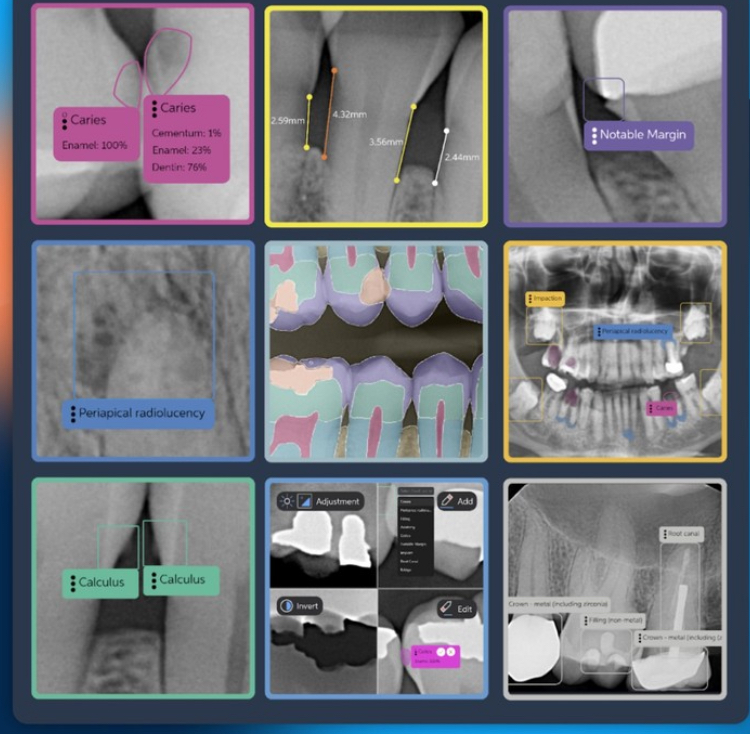

Precision Diagnostics with PearlAI: Our cutting-edge radiography system utilizes PearlAI to analyze your X-rays with incredible accuracy. This helps us detect even the smallest signs of dental issues like cavities, gum disease, and infections, often before they become visible to the naked eye. Early detection means less invasive treatments and better long-term oral health.